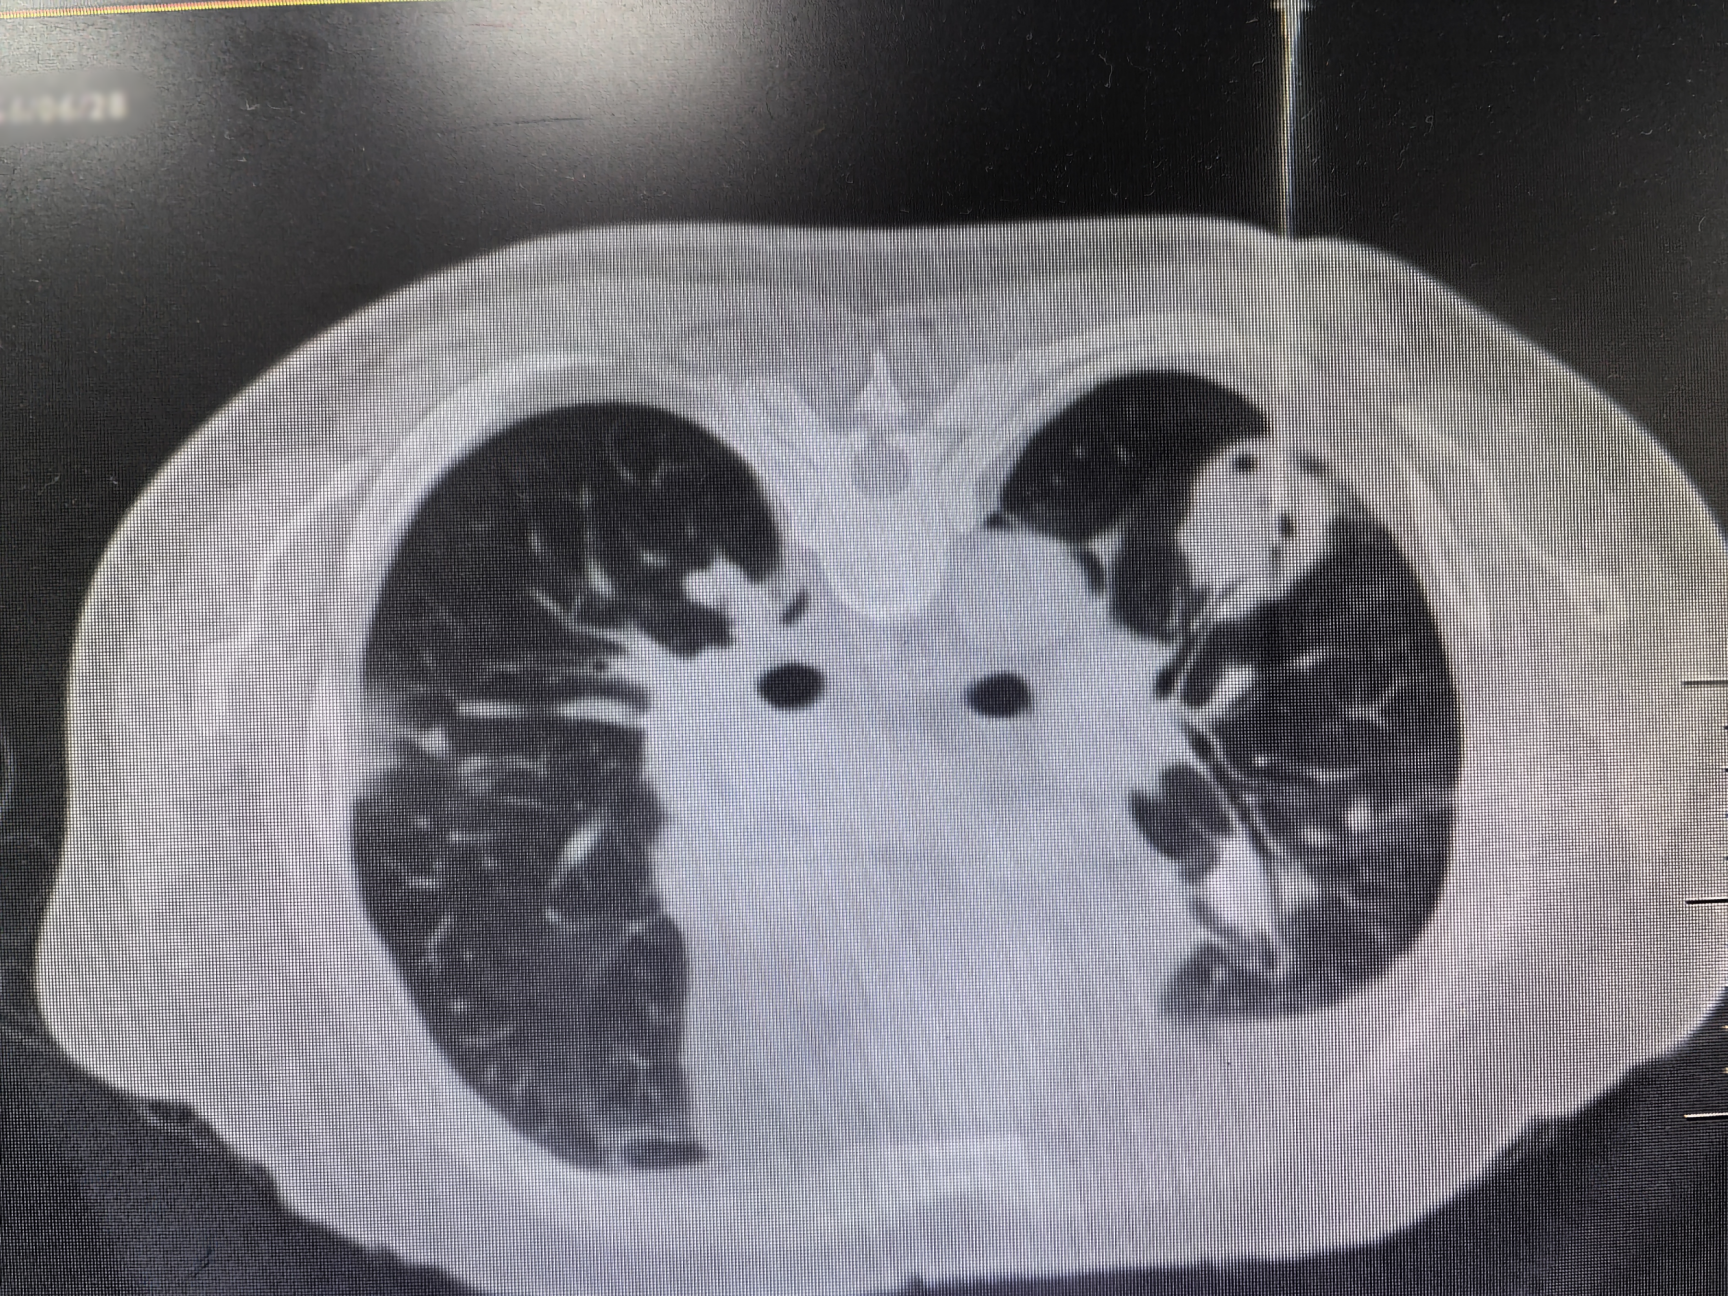

近日,昆明医科大学第二附属医院呼吸介入团队成功为一位双肺多发结节的老年男性患者开展医院首例双肺结节同步穿刺术,为患者明确诊断了“韦格纳肉芽肿病”这一罕见病。

与患者反复沟通病情后,患者最终同意再次进行肺活检。完善术前检查、排除肺活检禁忌证后,在呼吸介入团队医护配合下,陆霓虹博士为患者实施了高难度“双肺结节同步穿刺活检术”。手术仅用时12分钟,顺利获取病变组织,且患者无并发症。病理检查(ROSE)提示肉芽肿性病变,结合血液c-ANCA阳性,最终确诊为“韦格纳肉芽肿病”(WG)。经对症治疗,患者症状显著好转。

韦格纳肉芽肿病(WG)是一种特殊的坏死性肉芽肿性血管炎,病因不明。病变常累及多个器官,病理表现为肉芽肿性病变,伴血管壁炎症。因WG发病率较低,肺部病变常常被误诊为肺部肿瘤或者肺结核。2024年发表的中国肺结节规范化诊疗专家共识指出,双肺多发结节须进行双肺的活检取材,避免结节漏诊及误诊。双肺同步穿刺技术难度较高,对操作医师的熟练程度、操作技术水平均有要求。